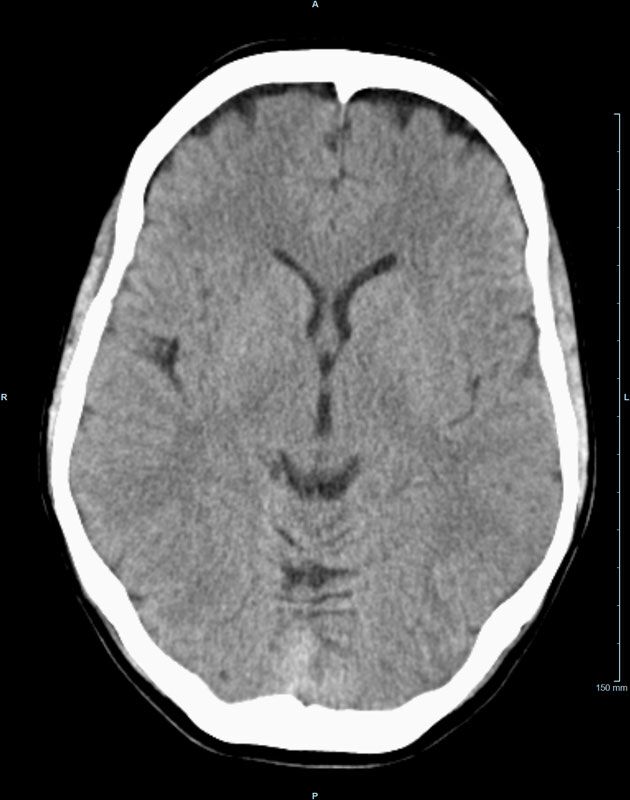

Kopf

• Schlaganfalldiagnostik

• Traumadiagnostik (Akutdiagnostik nach Verletzungen, Unfällen)

• Nasennebenhöhlen (Entzündungen, Tumore)